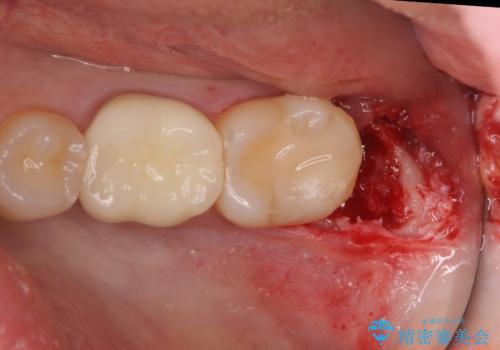

ただし、元のインレーが遠心マージンが縁下だったため、矯正治療後に歯ぐきの厚みを減らして、しっかり歯ぐきの上にマージンラインが来るように整える手術(ディスタルウェッジ)を行いました。

レーザーや電気メスで分厚い歯肉を焼いても一時的で、やがてまた元のように歯ぐきが上まで増殖しますので、今回は骨の厚みも調整し、7番の遠心を出来るだけ下げました。